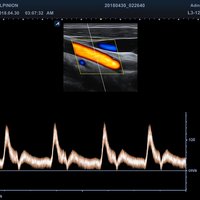

• PW-Doppler (Pulsed-Wave): Verfahren, das ein Geschwindigkeitsspektrum von beweglichem Gewebe und Flüssigkeiten an einer bestimmten Position liefert

• Farbdoppler: farbige Darstellung der Richtung des Blutflusses

• DPDI: Technologie, die Sensitivität des Powerdopplers mit der Flussrichtungsinformation des konventionellen Farbdopplers kombiniert